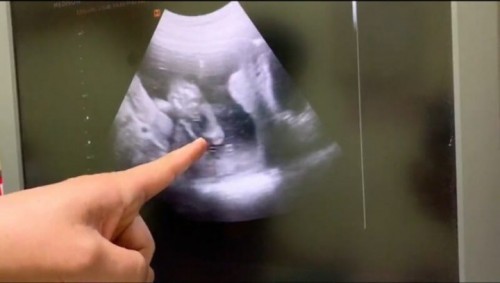

17w3d เพศหญิงหรือเพศชาย (ที่หมอชี้คือขา)

ซาวด์ตอนอายุครรภ์ 17w3d หมอบอกว่าอวัยวะเพศน้องยังเล็กอยู่ อยากถามความคิดเห็นของแม่ๆหน่อยค่ะว่าเพศหญิงหรือเพศชาย

ต้องถามหมอค่ะแม่เพราะรูปดูไม่ค่อยออก บ้านนี้คุณหมอบอกค่ะเพราะดูในรูปซาวด์ไม่รู้เรื่องเลย

ขนาดหมอยังบอกไม่ได้เลยค่ะ รูปอัลตร้าซาวด์ดูยาก รอเดือนหน้าค่อยซาวด์อีกทีนะคะ

17 ยังไม่เห็นคะ รอ 20 วีคขึ้นนะคะแม่

ต้องซาวด์อีกรอบ รอสัก 20 วิคค่ะ